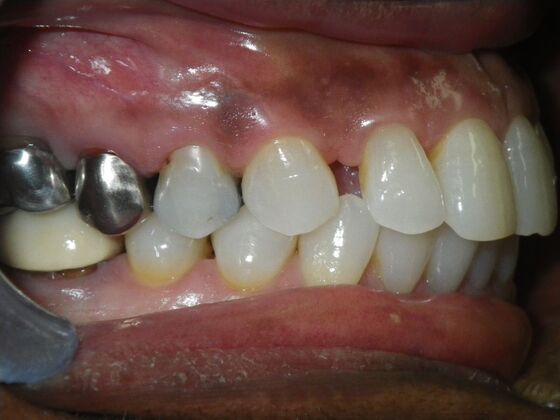

Patient wanted to close all spaces, especially upper right by her cuspid.